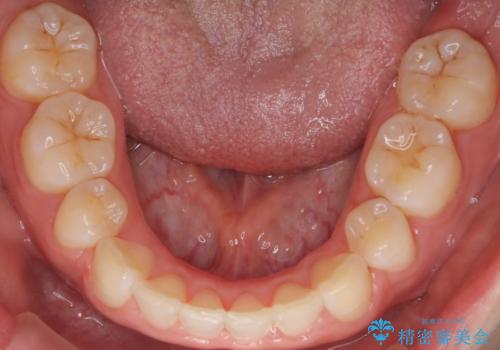

- 横から見たときの口元が出てるの気になるとのことで来院されました。

口元の突出感と口唇の閉じずらさが確認されました。

上下左右の歯を1本ずつ、合計4本抜歯しして前歯を後方に下げて、口元の突出感を改善する計画としました。

前歯をしっかり下げることで、口元がすっきりしました。